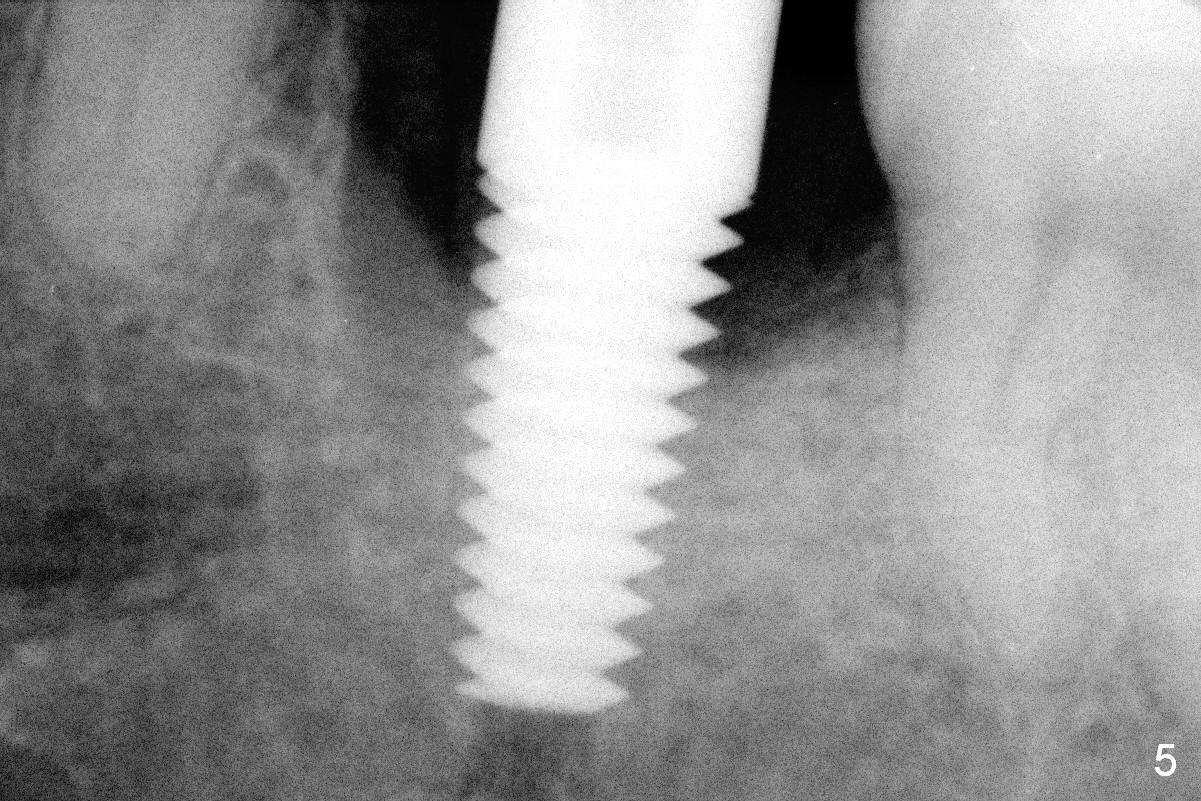

The mesial and distal crests of the tooth #19 were even for a 50-year-old man 7 years ago. Three years later, swelling developed around the distal root with bone loss (Fig.2 *). Three months later, localized swelling occurred (Fig.3 *) with oozing. The patient had thrombopenia (platelet 40 K). The tooth was extracted with suture. There is distolingual root tip resorption. Two months and a half later (Fig.4), a 6x17 mm implant was placed (Fig.5). The implant osteointegrated 5 months postop (Fig.6). The distal crest re-appears 5 months (Fig.7), 2 years (Fig.8) and 2 years 8 months (Fig.10) post cementation. At the last appointment, the patient complained of pain and swelling at #30 with mesial bone loss (Fig.10 *), as compared to Fig.9 taken 9 years ago. The mesiolingual pocket is deep. After scaling and Chlorhexidine irrigation, Arestin is locally administered.